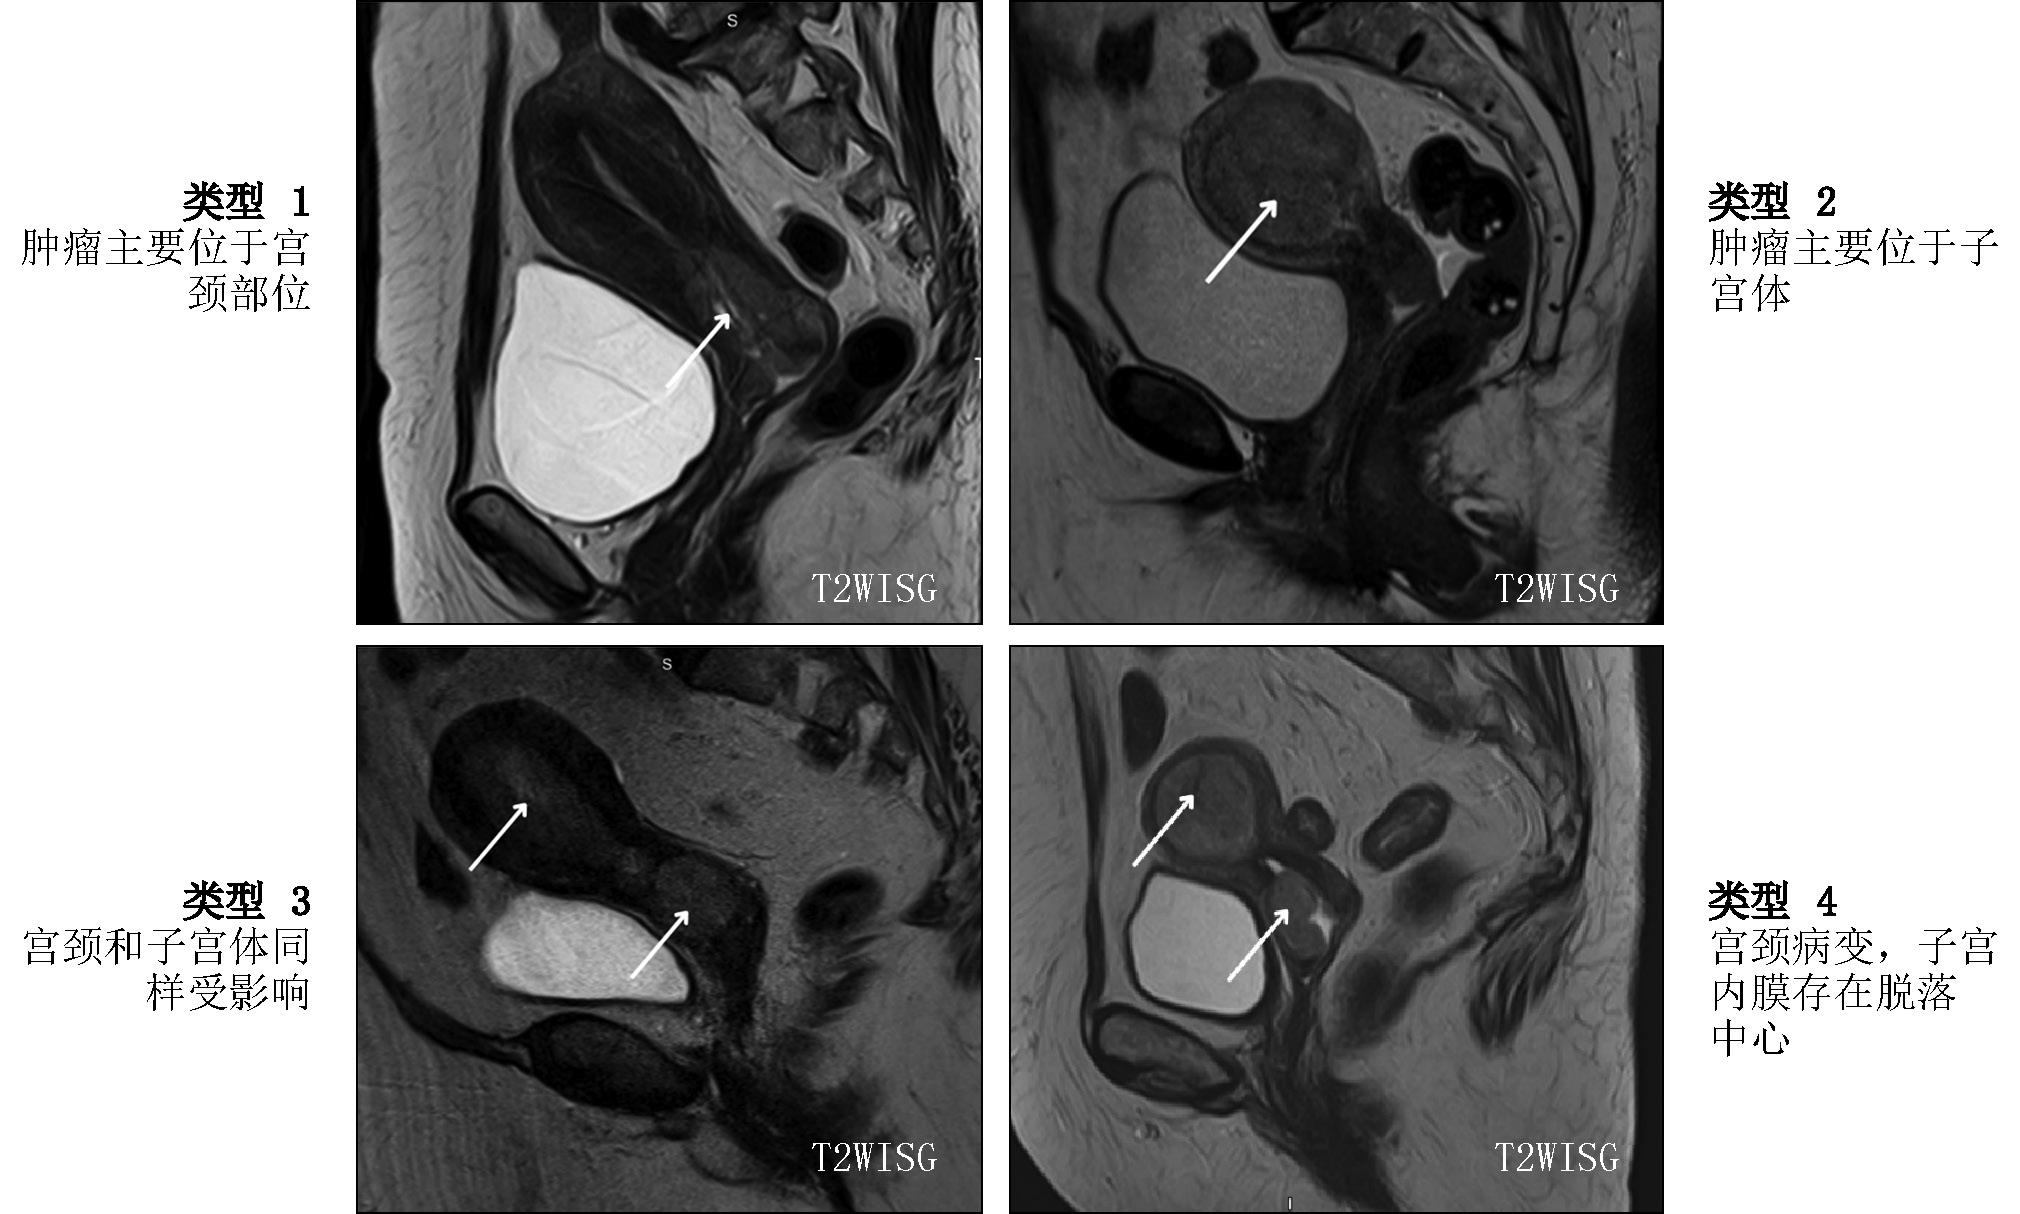

Differential diagnosis of the location of the primary tumor (whether the observed uterine abnormalities were endometrial carcinoma with cervical involvement or cervical carcinoma with endometrial involvement) was critical in the diagnostic search of gynecologists and radiologists for detecting uterine adenocarcinoma. All diagnostic controversies with predominant involvement in the uterine cavity were further reviewed by pathologists, and in all patients, endocervical adenocarcinoma (tumor of the cervix) was confirmed. Therefore, four types of tumor macrostructure were retrospectively classified based on the predominant location of the tumor according to MRI and pathology data (Fig. 4):

- Predominance of tumor in the cervix (n = 13; 65%)

- Predominance of tumor in the uterine body (n = 2; 10%)

- Equal involvement of endocervix and endometrium (n = 2; 10%)

- Isolated cervical lesion with CA lesion seeding into the uterine cavity (in the endometrium), confirmed by pathology and immunohistochemistry data (n = 3; 15%)

Fig. 4. Type of tumor macrostructure, T2-weighted images in sagittal plane, cervical adenocarcinoma.

Notably, type 2, 3, and 4 tumors were described as uterine body cancer on MRI, and only pathology examination confirmed primary CA.